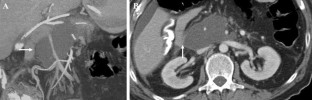

Fig. 7

Fig. 8